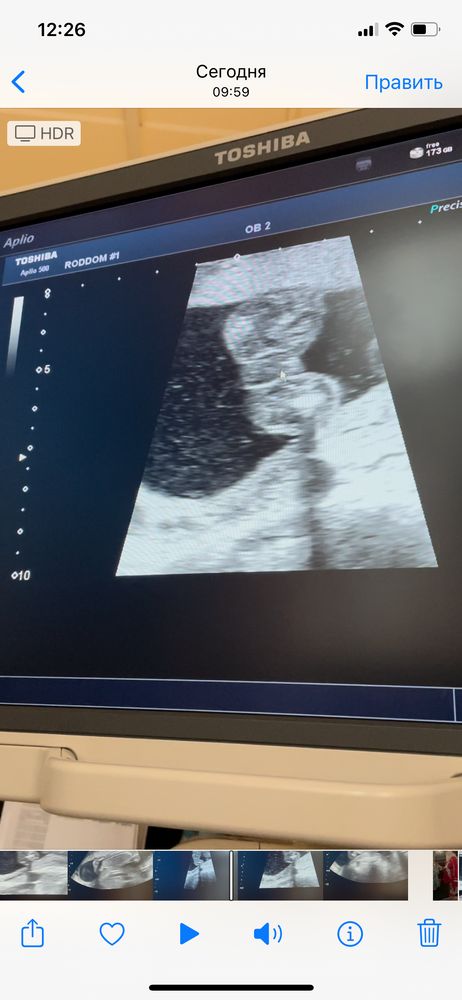

Изображение Яна , сегодня была на узи другом и там подтвердили мальчик

03.01.2022

Валерия Воробьева, ой на этом снимке не разберу , можно по дальше сфоткать? Вижу что то торчит но откуда торчит не пойму 😅 Да и странно что на таком сроке не говорят четко пол )

Яна , сегодня сказали что 💯 процентов мальчик. И вот то что торчит это писюн (обвела кружком ) Изображение

Валерия Воробьева, отлично ) Поздравляю вас с сыночком )) 🙌🏻